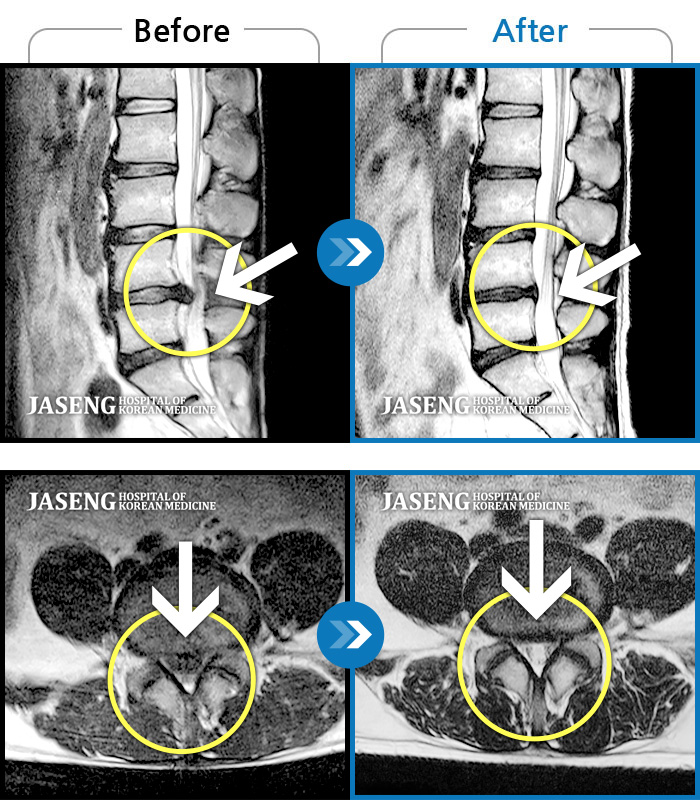

MRI 치료사례

극심한 요통과 다리 통증으로 허리가 휘어진 채 내원